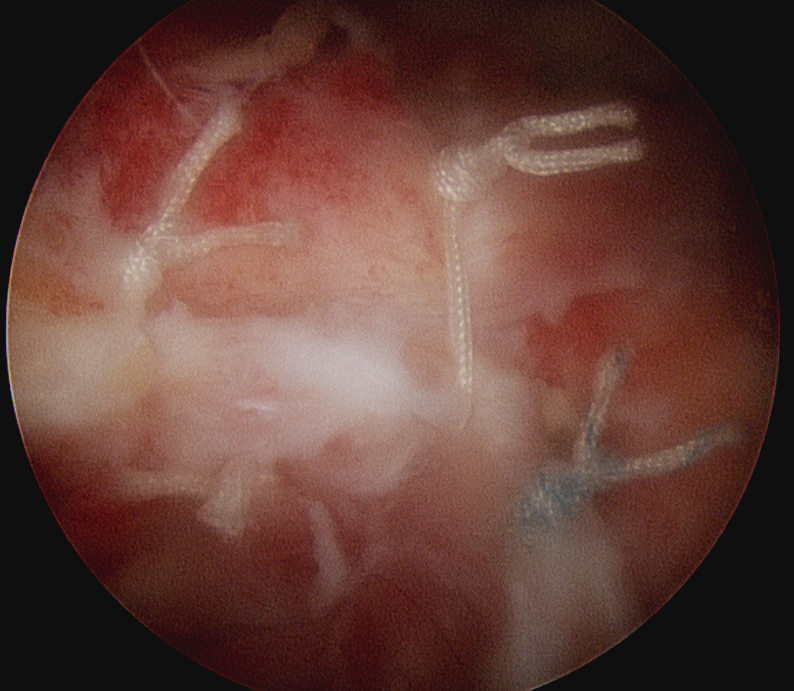

Margin convergence sutures

Release infraspinatus tendon posteriorly and assess mobility

Repair infraspinatus with a combination of margin convergence and posterior suture anchors onto posterior greater tuberosity

True partial repair of the rotator cuff with exposed triangle of greater tuberosity